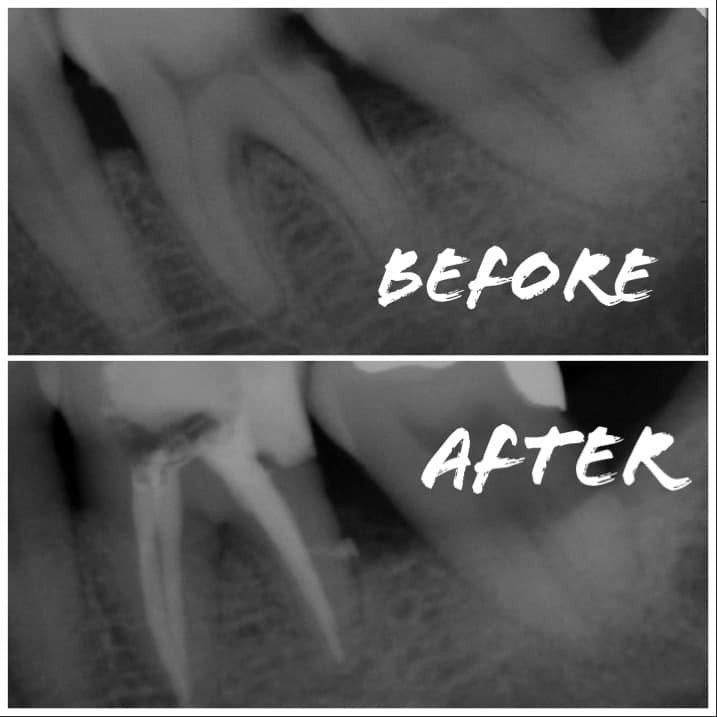

牙齒構造分為三層,最外層堅硬的琺瑯質,中間的牙本質,以及最裡面含有神經血管的牙髓腔。當蛀牙蛀得太深,細菌便會感染到牙髓腔,造成牙齒敏感疼痛、引起化膿,最後還會變成恐怖的 蜂窩性組織炎 呢!這時候就要趕快找醫師做 #根管治療(也就是俗稱的 #抽神經),才能終結您 #牙痛的惡夢

所謂根管治療,就是以精密器械將牙髓腔及底下根管裡的感染組織清除乾淨,才不會讓細菌沿著神經感染到牙齒外面的骨頭,造成根尖囊腫或 #蜂窩性組織炎 這類骨質結構的破壞。由於牙髓腔裡面的神經系統相當複雜,因此根管治療需要較長的療程,才能盡可能將感染源清除。此外,在根管治療時,為了避免神經再度被口腔的細菌感染,會將您的牙齒戴上橡皮障,隔離外界口水。根管治療完的牙齒,也建議做上假牙,才能保障牙齒的密封性以及結構強度喔!

另外,隨著醫療科技的提升,很多原本被判死刑的牙齒,也有福音了✨現在可以藉由 #顯微根管治療,以牙科專用的 #顯微鏡,將牙髓腔放大數十倍,清除肉眼難見的感染源,並提高根管治療的效率和成功率,讓您的治療結果更快、也更好!如果有需要,可以跟醫師做諮詢,讓我們一起努力,來幫您保留您的牙齒吧!